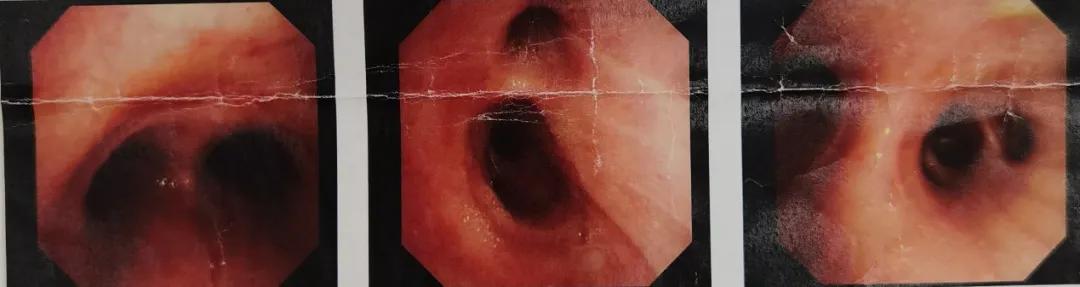

从左至右:隆突、右主支气管、右中间支气管

从左至右:左主支气管、左肺上叶支气管、左肺下叶支气管

图3:支气管镜检查(2020.05.09)